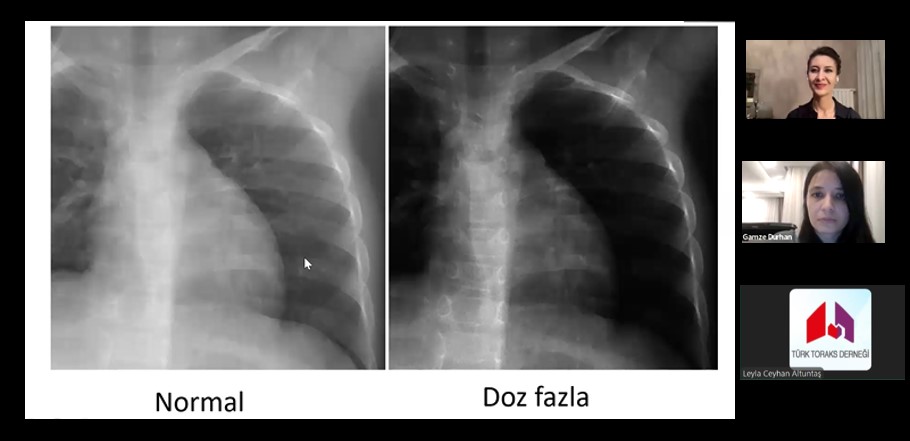

Türk Toraks Derneği Azerbaycan Temsilciliği Ocak Ayı Webinarı "Konvansiyel Akciğer Radyolojisi Değerlendirme" Başlığı ile Gerçekleştirildi

Aslıhan Gürün Kaya moderatörlüğünde; "Konvansiyel Akciğer Radyolojisi Değerlendirme" Gamze Durhan tarafından aktarıldı.